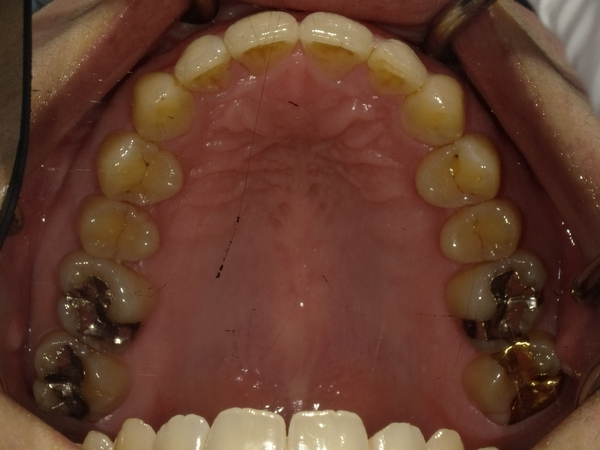

すきっぱ(空隙歯列)CASE4 2023.06.06 40代女性非抜歯BEFORE→AFTER〇ご相談内容:歯と歯の間があいている、下の歯のがたつき〇矯正の種類:マウスピース型矯正「インビザラインGO」〇治療期間:17週間〇治療費用:44万円(税込) < すきっぱ(空隙歯列)CASE5すきっ歯(空隙歯列弓)CASE3 > ブログ記事一覧をみる